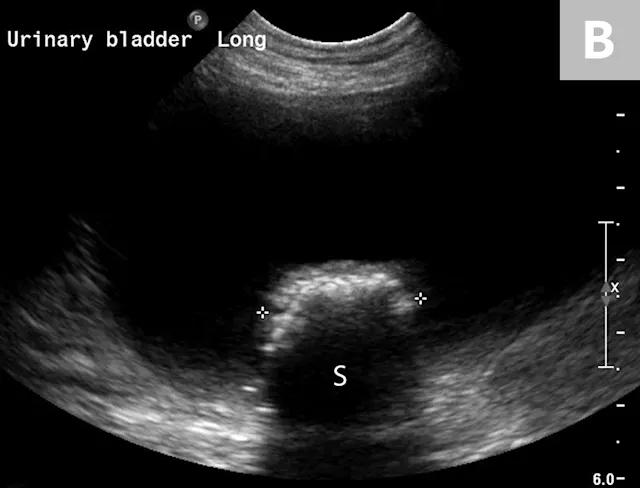

Calculi of the Urinary Bladder & Urethra

Calculi formation within the urinary bladder occurs from a variety of inherited and environmental conditions, and management is often imperative.7 Radiographic detection of urinary bladder calculi has up to 87% sensitivity with improvement to 95% when used in combination with positive-, negative-, or double-contrast cystography.15

The lower detection rates for survey radiography are largely due to the variations in the chemical composition of different calculi. The most common types of calculi in small animal practice are struvite and calcium oxalate; both are mineral opaque (Figure 8).13,14,16,17